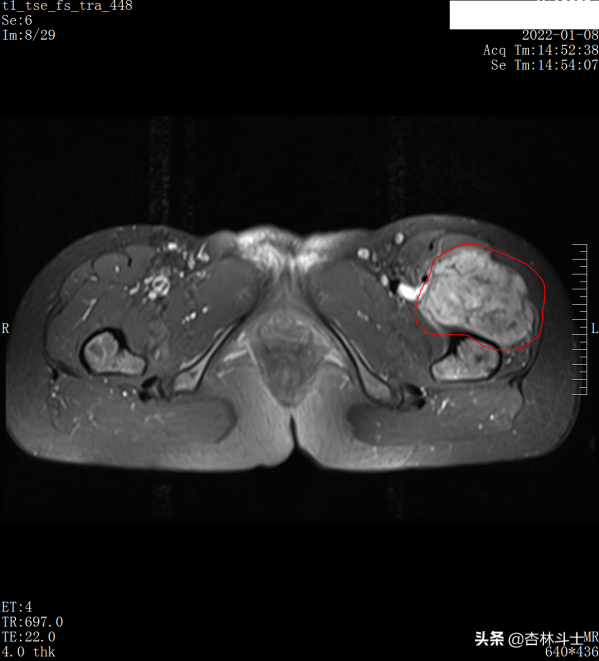

入院後查了左大腿3T磁共振平掃+增強,如圖示:

t2 橫斷位,左股骨上段前方不規則軟組織腫塊,與正常肌肉相比呈混雜稍高訊號